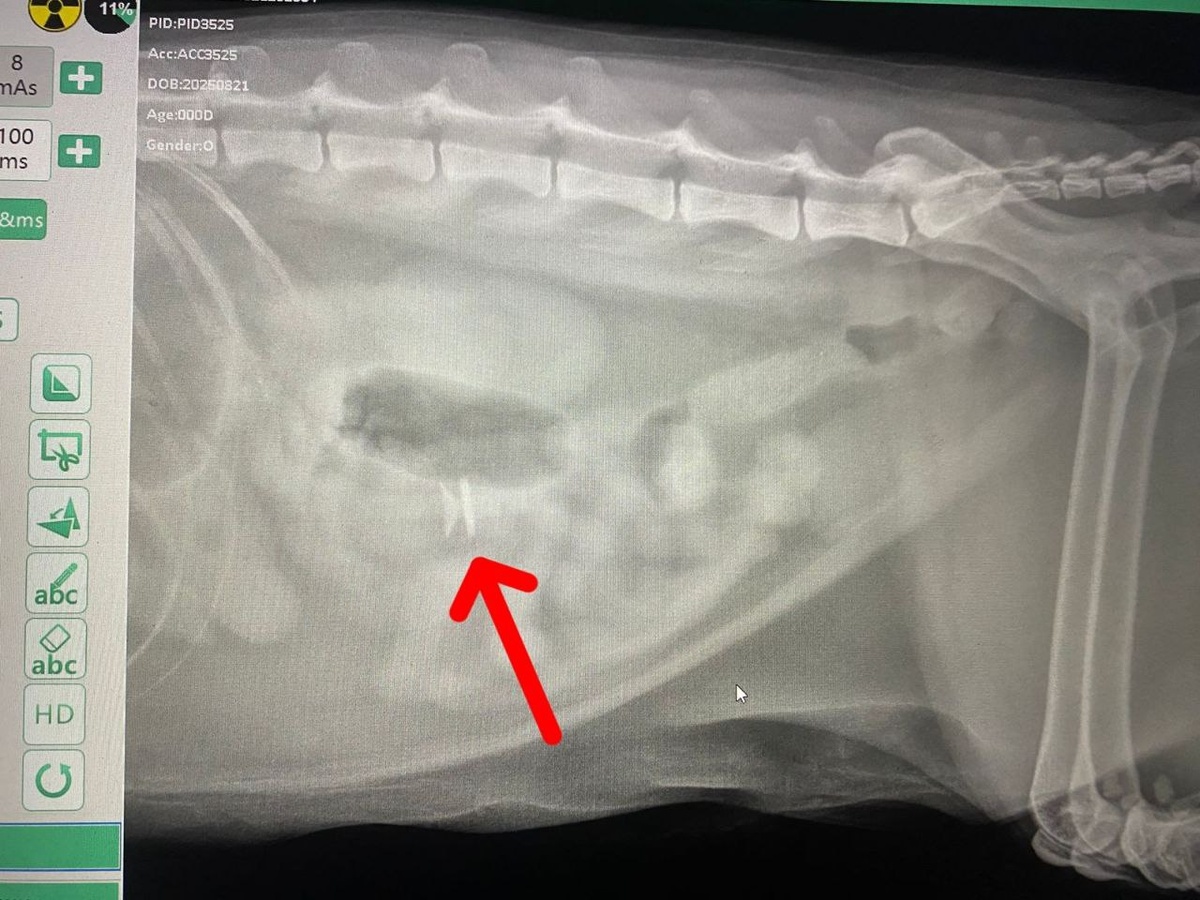

Ох уж эти котики! Тянут всякое в рот, как малые дети 👶👶🍼 Вот такой инородный предмет был обнаружен на рентгене. ❗Наши врачи провели срочную операцию, предмет извлекли (листайте карусель) Без него котику стало явно лучше 😉

Вот такой инородный предмет был обнаружен на рентгене.